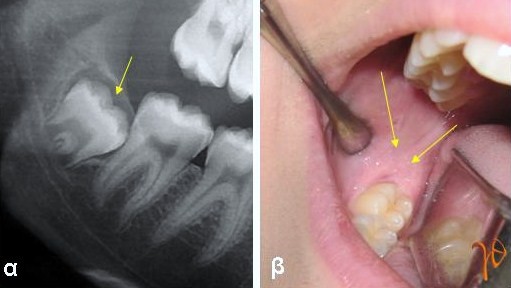

Οι πιο συχνές βλάβες στο στόμα είναι τα αποστήματα, τα οποία όταν οφείλονται σε μικροβιακές λοιμώξεις δοντιών της άνω γνάθου μπορούν να εκδηλώνονται και στην υπερώα (Εικόνα 3). Η θεραπεία τους προϋποθέτει την θεραπεία του υπεύθυνου δοντιού.

Εικόνα 3. α. Απόστημα που οφείλεται σε γομφίο οδόντα (βέλος), β. Απόστημα που οφείλεται σε τομέα οδόντα (βέλος).